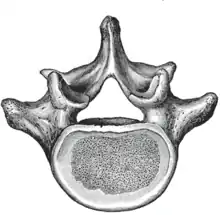

The adjacent figure depicts the general characteristics of the first through fourth lumbar vertebrae. The fifth vertebra contains certain peculiarities, which are detailed below.

As with other vertebrae, each lumbar vertebra consists of a vertebral body and a vertebral arch. The vertebral arch, consisting of a pair of pedicles and a pair of laminae, encloses the vertebral foramen (opening) and supports seven processes.

Body

The vertebral body of each lumbar vertebra is kidney shaped, wider from side to side than from front to back, and a little thicker in front than in back. It is flattened or slightly concave above and below, concave behind, and deeply constricted in front and at the sides.[1]

Arch

The pedicles are very strong, directed backward from the upper part of the vertebral body; consequently, the inferior vertebral notches are of considerable depth.[1] The pedicles change in morphology from the upper lumbar to the lower lumbar. They increase in sagittal width from 9 mm to up to 18 mm at L5. They increase in angulation in the axial plane from 10 degrees to 20 degrees by L5. The pedicle is sometimes used as a portal of entrance into the vertebral body for fixation with pedicle screws or for placement of bone cement as with kyphoplasty or vertebroplasty.

The laminae are broad, short, and strong.[1] They form the posterior portion of the vertebral arch. In the upper lumbar region the lamina are taller than wide but in the lower lumbar vertebra the lamina are wider than tall. The lamina connects the spinous process to the pedicles.

The vertebral foramen within the arch is triangular, larger than the thoracic vertebrae, but smaller than in the cervical vertebrae.[1]

Processes

The spinous process is thick, broad, and somewhat quadrilateral; it projects backward and ends in a rough, uneven border, thickest below where it is occasionally notched.[1]

The superior and inferior articular processes are well-defined, projecting respectively upward and downward from the junctions of pedicles and laminae. The facets on the superior processes are concave, and look backward and medialward; those on the inferior are convex, and are directed forward and lateralward. The former are wider apart than the latter since in the articulated column, the inferior articular processes are embraced by the superior processes of the subjacent vertebra.[1]

The transverse processes are long and slender. They are horizontal in the upper three lumbar vertebrae and incline a little upward in the lower two. In the upper three vertebrae they arise from the junctions of the pedicles and laminae, but in the lower two they are set farther forward and spring from the pedicles and posterior parts of the vertebral bodies. They are situated in front of the articular processes instead of behind them as in the thoracic vertebrae, and are homologous with the ribs.[1]

Three portions or tubercles can be noticed in a transverse process of a lower lumbar vertebrae: the lateral or costiform process, the mammillary process, and the accessory process.[2] The costiform is lateral, the mammillary is superior (cranial), and the accessory is inferior (caudal). The mammillary is connected in the lumbar region with the back part of the superior articular process. The accessory process is situated at the back part of the base of the transverse process. The tallest and thickest costiform process is usually that of L5.[2]